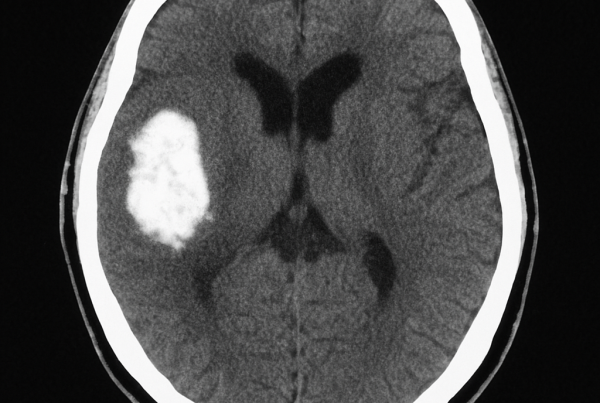

Trombectomía mecánica ACV

La trombectomía mecánica ACV representa uno de los mayores avances…